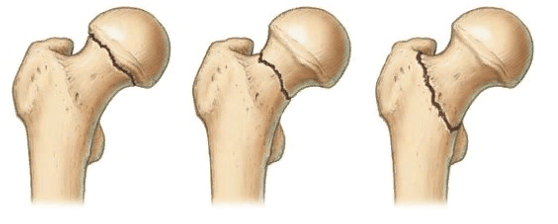

Показания к остеотомии

Клиническая потребность в операции возникает, когда у взрослых или детей диагностируются выраженные расстройства функций опорно-двигательного аппарата, болевые ощущения при наличии деформирующих признаков. В области ТБС деформации сформированы на фоне врожденных и приобретенных дисплазий, вторичных и возрастных дегенеративных изменений хрящевых, костных тканей. Распространенными показаниями для назначения остеотомии бедренной кости в данном случае являются:

- варусная деформация шейки;

- вальгус шейки бедра;

- псевдоартроз шейки бедренной кости; ;

- неправильно сросшийся перелом;

Локализация наиболее распространенных переломов.